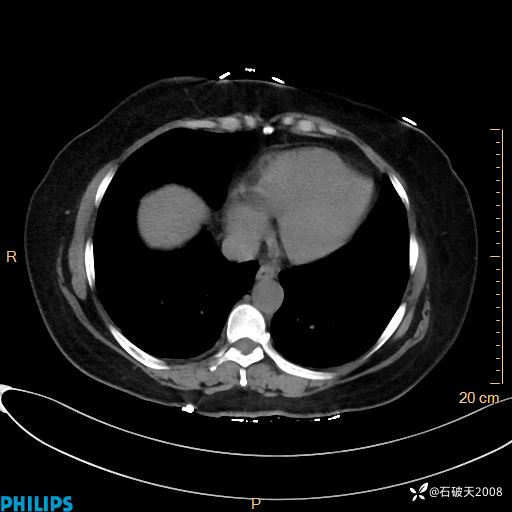

肺结节病?纵膈型肺癌?淋巴瘤?有点意思,欢迎围观

女 52岁 主 诉:咳嗽10余天,咳痰2天。

现病史:10余天前无明显诱因出现咳嗽,呈阵发性干咳,伴咽喉部发痒,无咽痛,无咳痰,无鼻塞、流涕、打喷嚏,无发热、畏寒、寒颤,无头痛、头晕,无胸闷、胸痛,无反酸、烧心,无腹痛、腹泻,无尿频、尿急,无皮疹等,在当地诊所求治,给予口服药物治疗(具体不详),病情无好转。遂在当地社区卫生服务中心开具口服药物治疗(具体不详),疗效欠佳。2天前出现咳痰,在我院门诊求治,行胸部CT提示肺部感染,建议住院,患者要求口服药物治疗,目前仍咳嗽、咳白色粘痰,白天量多,夜间自觉喉部喘鸣音,遂再次来院就诊,以“肺部感染”为诊断收入院。发病以来,神志清,精神可,饮食可,夜间睡眠差,大小便正常,近期体重无明显变化。

纵隔窗